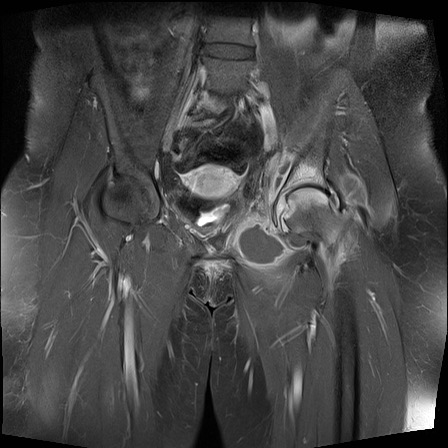

Hình ảnh X-quang khung chậu của bệnh nhân viêm khớp do lao tại khớp háng trái.

Có hẹp khe khớp kín đáo kèm theo xơ cứng dưới sụn tại khớp háng trái.

Các dấu hiệu X-quang này không đặc hiệu và rất có thể là biểu hiện của thoái hóa khớp.

Tiếp tục xem hình ảnh MRI…

Điều bất ngờ với tất cả mọi người là có nhiều ổ áp-xe.

Khi hình thành áp-xe lan rộng như vậy trong khi biểu hiện lâm sàng lại tối thiểu, cần luôn nghĩ đến viêm khớp do lao.

Chẩn đoán viêm khớp do lao được xác lập bằng chọc hút dịch khớp.